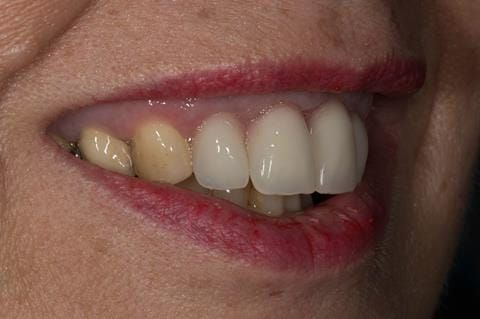

- High smile line showing gum above gingival zeniths of upper front teeth when smiling. Aesthetic failure of the upper four incisors with inflammation of the gingivae and mis-match of the gingival zenith levels.

- Extract the upper 2-2 teeth and replace with an interim acrylic based partial denture. Reline the interim denture over 9 - 12 months, replacing with a definitive cobalt chromium based partial denture. The definitive denture would ideally be designed as an occlusal protective splint to reduce the the potential for mechanical wear and breakages of the moderately/heavily restored maxillary dentition. In addition, should further upper teeth require extraction they could be added on to the denture cobalt chromium framework - therefore a new prosthesis would not be required as future teeth are lost. This option would produce an excellent aesthetic outcome. This is the option the patient chose to have.

Following consultation and second discussion appointment the patient chose to have option 3 namely, a maxillary cobalt chromium based partial denture/protective occlusal splint. The clinical situation and treatment process is shown in detail below with photographs. The patient was successfully rehabilitated with this and her quality of life considerably improved. The clinical work was provided by Finlay and the technical work by Rowan.